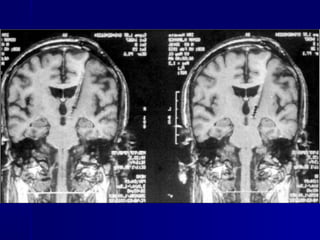

NEURONAVEGAÇÃO

Advances in Surgery l September 9, 2006 l 51

Como minimizar riscos e

maximizar a ressecção ?

Neuronavegação

Mapeamento Funcional

Imagem Intraoperatória

Avanços nas Técnicas

cirúrgicas